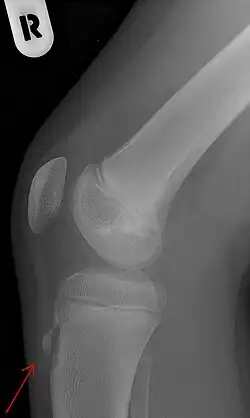

Röntgenaufnahme mit dem Befund eines Morbus Osgood-Schlatter

Eine Bildgebung kommt bei atypischer Symptomatik in Betracht, dann je nach Fragestellung und Differentialdiagnose Sonographie des Sehnenansatzes (DD:Bursitis, Abszess), eine Röntgenaufnahme seitlich oder selten eine Kernspintomographie. Diagnostische Kriterien sind dann Fragmentation der Tuberositas, Auftreibung der ansetzenden Sehne, Weichteilödem sowie im MRT angrenzende Ödeme in der Tibia.